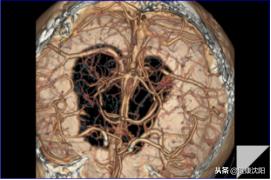

VR三维显示可以直观显示血管的大体形态、解剖,可以对病变进行明确的定位、定性诊断,可以直观地显示血管狭窄、血管瘤、动静脉畸形等病变,还可以间接判断血管壁的病变,进而提供进一步检查的必要性。CTA检查的VR技术实现了无创检查就能了解自己血管形态的目的。

显示颅内血管的解剖及病变